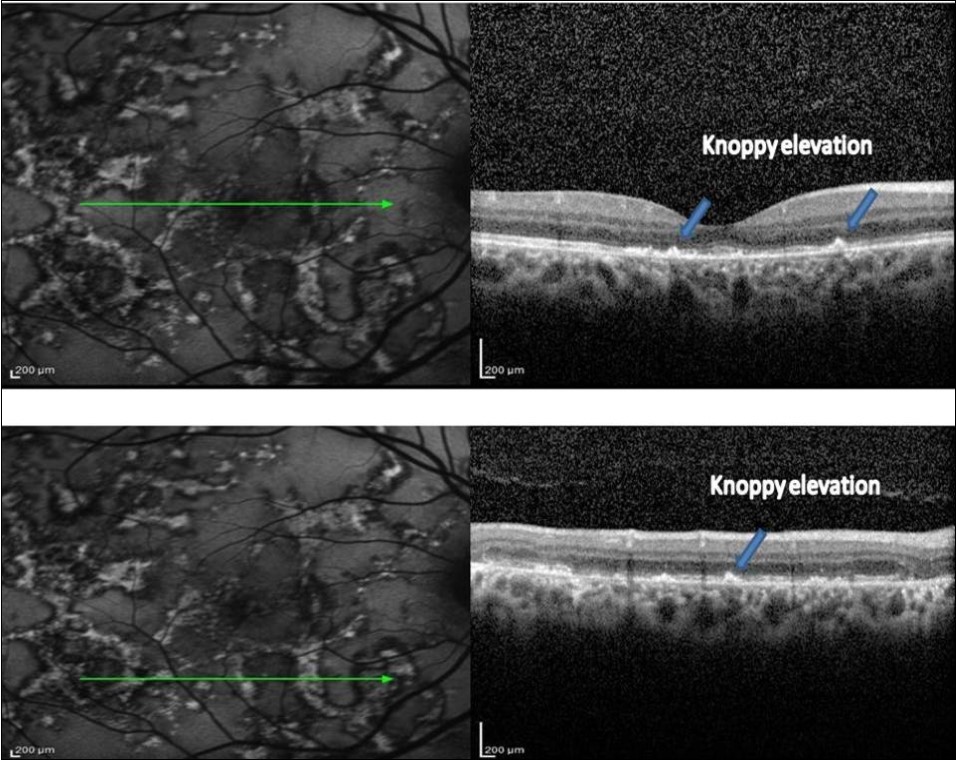

2. As the lesions started to heal, they became well defined and acquired a thin border of hypoautofluorescence while remaining predominant hyperautofluorescent centrally. The SD-OCT scan through the hyperautofluorescent area showed disappearance of the hyperreflective fuzzy areas that were replaced by irregular, hyperreflective knobbly elevations of the outer retinal layers. The RPE, the POST, IS/OS junction, and the ELM could not be distinguished. The ONL appeared normal. At this stage, there was an increased reflectance from the choroidal layers due to attenuating RPE–photoreceptor complex.

A 34-year-old male presented with decreased vision in Right eye since one and half month. On examination, the BCVA was 6/ 60 and 6/6 in the right and left eyes, respectively. Both eyes showed unremarkable anterior segment and multifocal lesions of active as well as inactive choroiditis in the posterior pole of Right eye and healed choroditis on left eye (Figure 1). Simultaneous FAF and SD-OCT imaging of the right eye revealed findings as explained in the “Results” Section (1.) (Figure 2). The tuberculin skin test was positive. He received four-drug antitubercular therapy with oral corticosteroids. About 2 weeks later, the lesions started to heal and appeared as described in “Results” Section (2.) (Figure 3). Three months later, the lesions healed further and appeared as explained in “Results” Section (3.) (Figure 4). Figure 5, Figure 6.

Figure 3.FAF (left) and corresponding eye-tracked SD-OCT image (right) of patient 1 during healing stage of the right eye shows hyperreflective knobbly elevations of the outer retinal layers. The RPE, the POST, IS/OS junction, and the ELM could not be distinguished. The ONL appeared normal with increased reflectance from the choroidal layers.